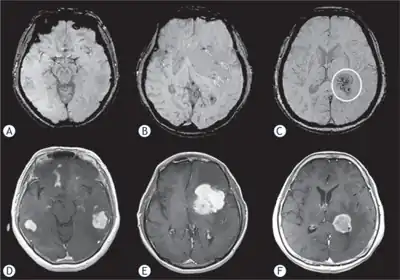

MRI or contrast enhanced CT classically shows multiple ring-enhancing lesions in the deep white matter. The major differential diagnosis (based on imaging) is cerebral toxoplasmosis, which is also prevalent in AIDS patients and also presents with a ring-enhanced lesion, although toxoplasmosis generally presents with more lesions and the contrast enhancement is typically more pronounced. Imaging techniques cannot distinguish the two conditions with certainty, and cannot exclude other diagnoses. Thus, patients undergo a brain biopsy or vitreous biopsy, if there is intraocular involvement.[11]